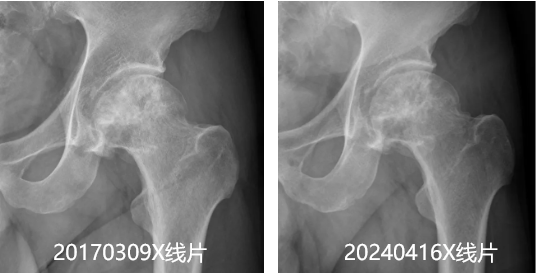

近日,长期在苏州工作生活的睢宁籍股骨头坏死患者王先生,专程前往优米app下载ios介入科进行复查。经过一系列摄线片、及检查,结果显示王先生的左股骨头坏死情况较七年前不仅...